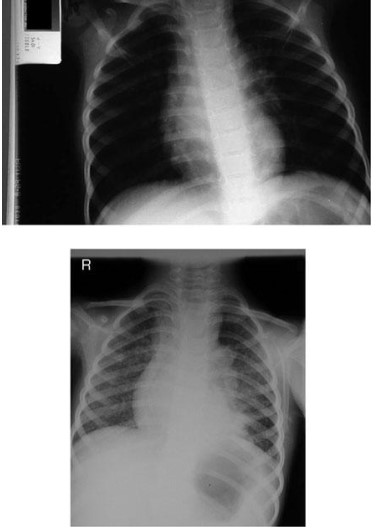

Common X-ray Findings: